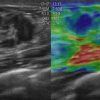

Ung thư vú

» Thông tin: Nữ giới – 25 tuổi.

» Lâm sàng: Khối tuyến vú.